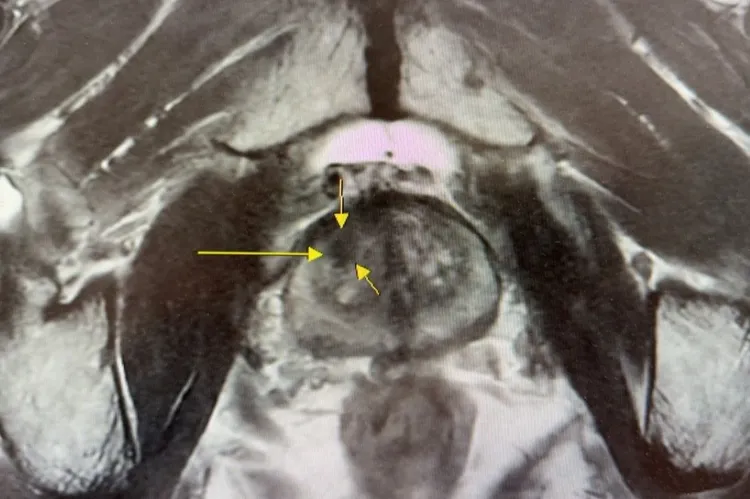

为提升诊断准确度,北慈以「核磁造影与超音波影像融合切片」取代传统随机切片,准确率提升6至7成,让病灶能在扩散前就被发现。早期患者5年存活率可达9成,即使是第4期患者,5年存活率仍接近6成。医疗团队也整合手术、放射线、化疗、贺尔蒙与标靶治疗,兼顾存活期与生活品质。医师提醒,排尿异常别只当老化,有家族史者更应及早检查,把握治疗黄金期。